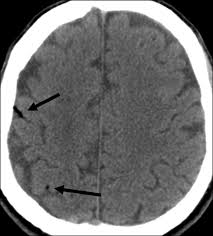

imaging findings in CJD

pulvinar & hockey stick signs (bilateral FLAIR hyperintensities in pulvinar & medial thalamus)

cortical diffusion restriction